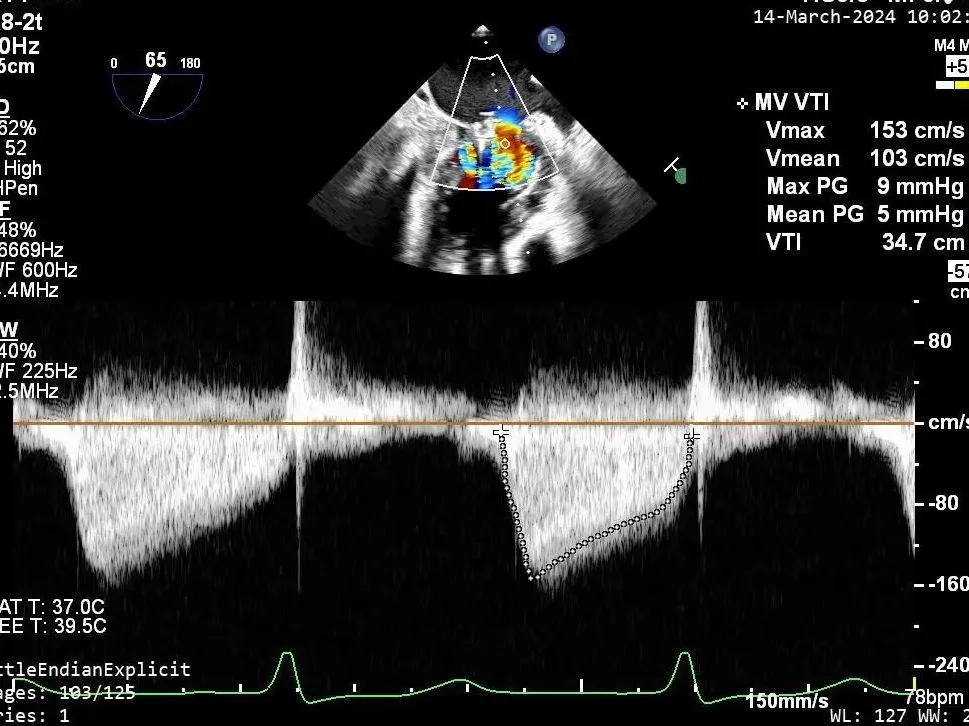

瓣膜夹释放前评估,二尖瓣平均跨瓣压差及瓣口面积

第二个瓣膜夹释放前评估,二尖瓣平均跨瓣压差及瓣口面积

第三个瓣膜夹释放前评估,二尖瓣平均跨瓣压差

PISA法测r=12mm,EROA=0.72cm2,RVOL=100ml,RF 26%。LVEDD 57mm,左房71*59*77mm,右房55*69mm,LVEF 70%。

二尖瓣后叶活动受限,呈房源性栓系,以P3区为重,二尖瓣前叶假性脱垂,二尖瓣瓣环前后径49mm,左右径40mm。